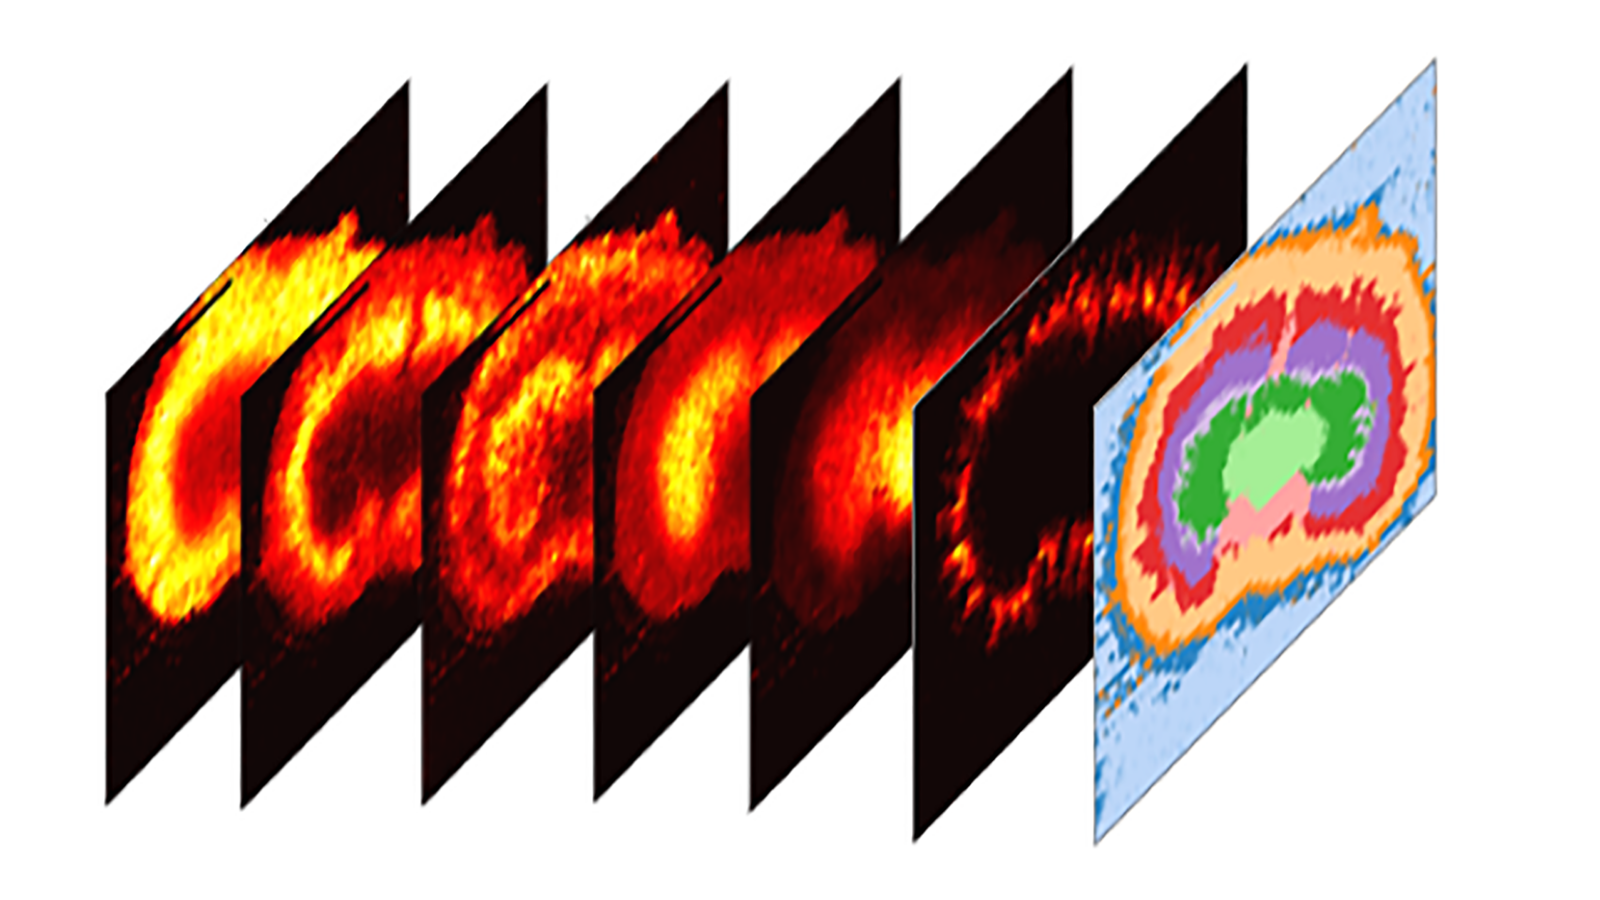

Maps of imaging mass spectrometry data from rat brain, courtesy of Hang Hu at PNNL

MALDI mass spectrometry image that shows where three kinds of lipids are in different parts of a human male kidney, courtesy of Dr. Elizabeth Neuman of Vanderbilt